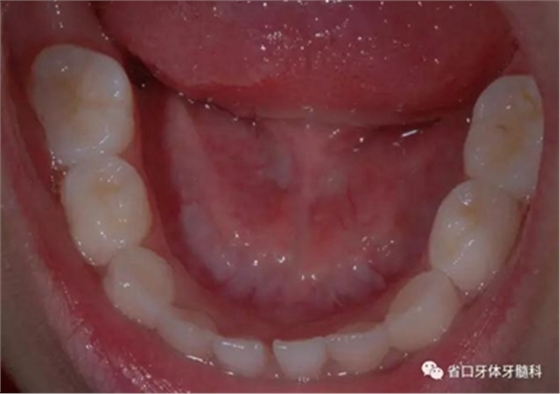

圖8 下頜牙相